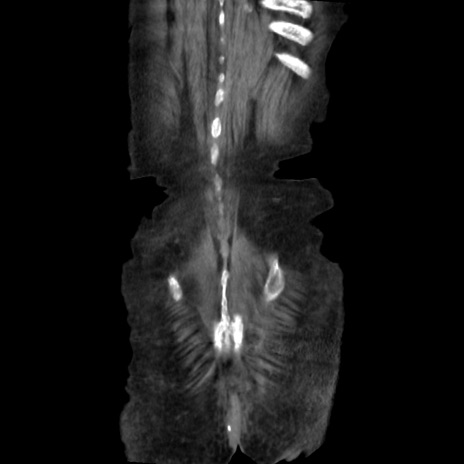

矢状断像